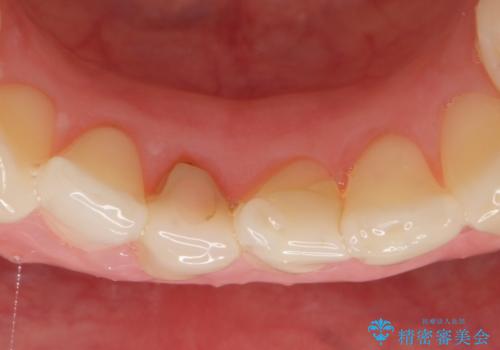

- 下顎前歯の見た目が気になるといらっしゃった方の症例です。

右下1の再根管治療終了後、オールセラミッククラウン(スペシャル)による補綴を行いました。

前歯の補綴ではオールセラミッククラウンを希望される患者様が多いですが、オールセラミッククラウンの中でも、エコノミー、スタンダード、スペシャル、エクセレントとランクがあります。

その中でも特に審美性が高いのがスペシャル、エクセレントです。スペシャル、エクセレントは口腔内写真をもとに熟練の技工士が、患者様の口腔内に合わせたオーダーメイドのクラウンを製作致します。